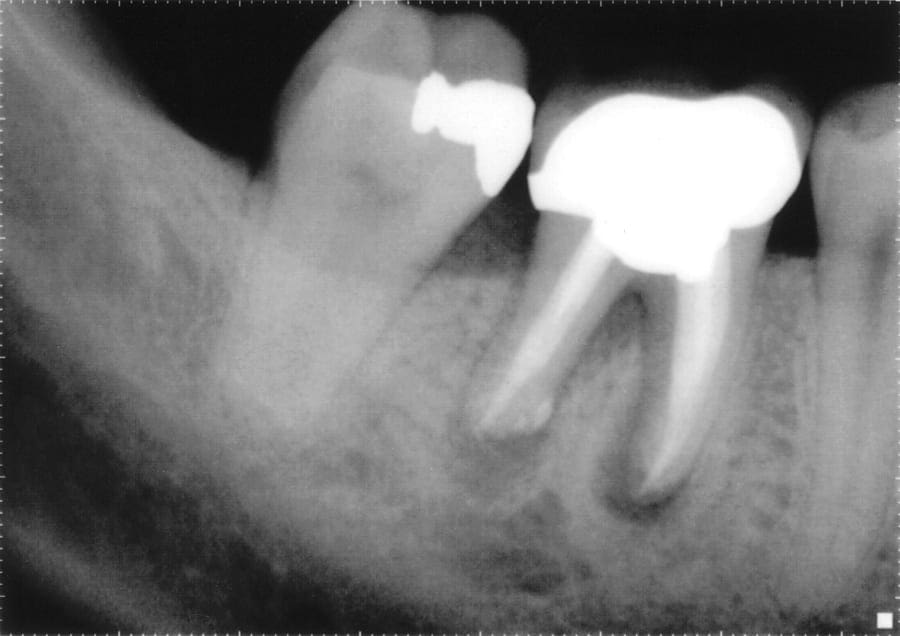

The telltale signs of failed root canal with Xray pictures Failed Root Canal Surgery Your endodontist will treat the infection, then fill. Unlike traditional root canal treatment, an apicoectomy is a surgical approach through the gum. For example, if your tooth is very damaged, a root canal may not solve your. After the area is thoroughly numbed with. Richard mounce describes the management of a failed root canal, placing emphasis on diagnosis, restorability,. Why. Failed Root Canal Surgery.

The telltale signs of failed root canal with Xray pictures Failed Root Canal Surgery Your nyc endodontist has several options, including root canal retreatment, extraction and apicoectomy. Unlike traditional root canal treatment, an apicoectomy is a surgical approach through the gum. Sometimes root canals fail because they weren’t the right solution for your tooth infection. Richard mounce describes the management of a failed root canal, placing emphasis on diagnosis, restorability,. Retreatment has the highest. Failed Root Canal Surgery.